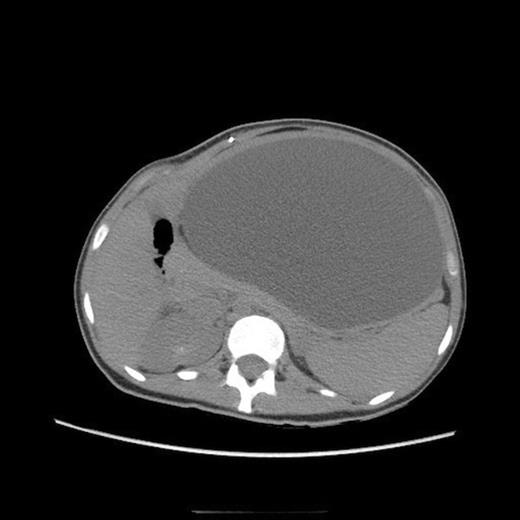

One-month follow up abdominal CT demonstrating recurrent formation of abdominal pseudocyst

The patient underwent laparoscopic cyst drainage with removal of the cyst wall. A total of 12.7L of fluid was drained. Culture results and routine labs were all negative. A post-operative CT demonstrated complete resolution of the fluid compartment (Fig. 4). The VP shunt catheter was initially left in the abdominal cavity. One month later, however, she developed significant recurrence of fluid collection (Fig. 5) and lethargy from malfunction of the VP shunt. The recurrent fluid was drained under ultrasound guidance, and her abdominal shunt catheter was removed. A new shunt catheter was placed in the right atrium, and the patient made a full recovery without any further complications.